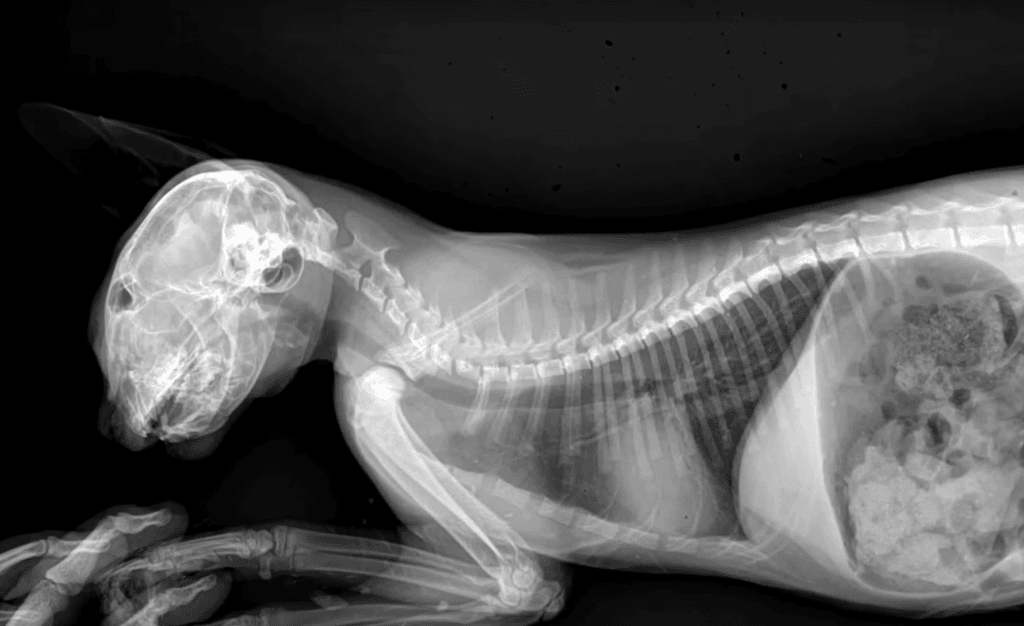

The initial examination revealed that Feyra was not only struggling to breathe, but she also had broken teeth, skull fractures, and fluid in her lungs.